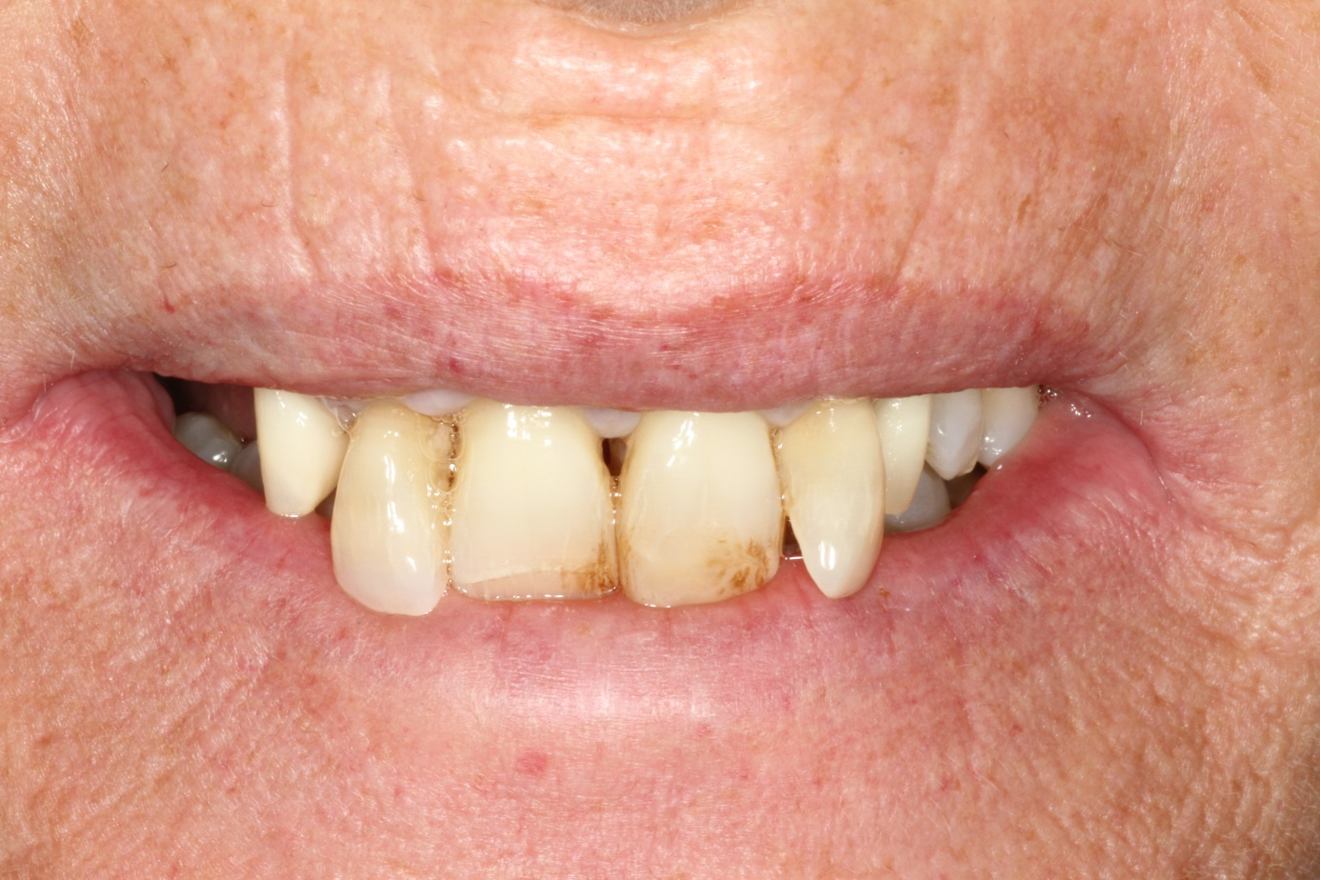

The 58-year-old, non-smoking and systemically healthy female patient was referred by her dentist to our dental clinic for implant treatment. The patient’s main complaints were poor aesthetics in the upper jaw, including a high smile line and distinct tooth pattern anomalies in the anterior maxilla (Figs. 1 & 2), as well as masticatory discomfort. Teeth #17, 15 and 27 were missing and had not undergone any prosthetic treatment, whereas the five missing teeth in the premolar and molar areas on both sides of the mandible had been replaced with a removable partial denture. All remaining teeth were affected by Stage IV periodontitis according to the 2017 Classification of Periodontal and Peri‐implant Diseases and Conditions, displaying a mean periodontal pocket depth of 5.6 mm.7 Mean bleeding on probing and mean plaque index were 70% and 80%, respectively. With respect to periodontal parameters, as well as to oral hygiene measures (visible calculus and dental plaque), the patient’s oral hygiene was graded as poor. The patient had been treated elsewhere with two implants in the posterior maxilla in order to replace the right first premolar and first molar (Fig. 3). She had a thick flat biotype, according to a definition introduced in 1977.8, 9

After obtaining informed consent from the patient, we would start dental rehabilitation in the maxilla, and we opted for a two-stage surgical approach after initial therapy. Initial therapy would consist of systematic periodontal treatment and regular recalls with instructions and checks for dental hygiene over a period of three months. The first stage of rehabilitation of the maxilla would consist of partial extraction therapy in conjunction with Type 1 implant placement in the regions of the teeth #12 and 22 according to the Proceedings of the Fourth ITI Consensus Conference and ridge preservation in the region of teeth #24 and 25 with particulate dentine, obtained and processed from the two extracted left maxillary premolar teeth.10 Owing to increased tooth mobility and the obvious poor buccal bone volume, as displayed on the CBCT scan (CRANEX 3D Ceph, Soredex, KaVo Kerr), regions #11 and 21 were not suitable for the socket shield technique in conjunction with implant placement (Fig. 4). Both central incisors were to be treated with the submerged root technique instead, in order to prevent damage of the buccal socket wall and volume loss of the alveolar ridge after tooth extraction. With both roots in place, a physiological pontic site development for the definitive restoration would be enabled. Based on periodontal re-evaluation after the initial therapy, only the two maxillary canines were considered worth preserving. The left first molar was to be temporarily retained in order to serve, in conjunction with the two canines, as an additional abutment tooth for fixation of the temporary bridge during the healing period. Crown preparation of the three remaining teeth would be done before surgical treatment, in order to prefabricate a temporary bridge for immediate fixed provisionalisation after the first surgery. The second surgical stage would consist ofimplant placement in region #24, performing of the socket shield technique on the mesiobuccal root, submersion of the distobuccal root and extraction of the palatal root of tooth #26 before immediate implant placement. Definitive prosthetic treatment would be performed after a transgingival implant healing period of at least three months, applying a conventional implant loading protocol with fixed bridges.11